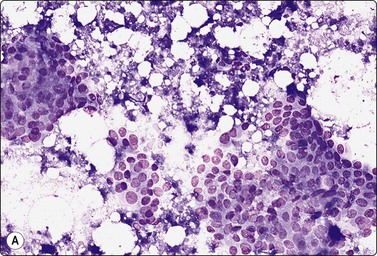

image image

Fig. 7.1 Radiation-induced atypia

(A) The epithelial cells in this irregular cluster show considerable nuclear enlargement, pleomorphism and hyperchromasia, but also some degenerative changes such as loss of nuclear structure (MGG, HP); (B) Corresponding tissue section (H&E, IP).